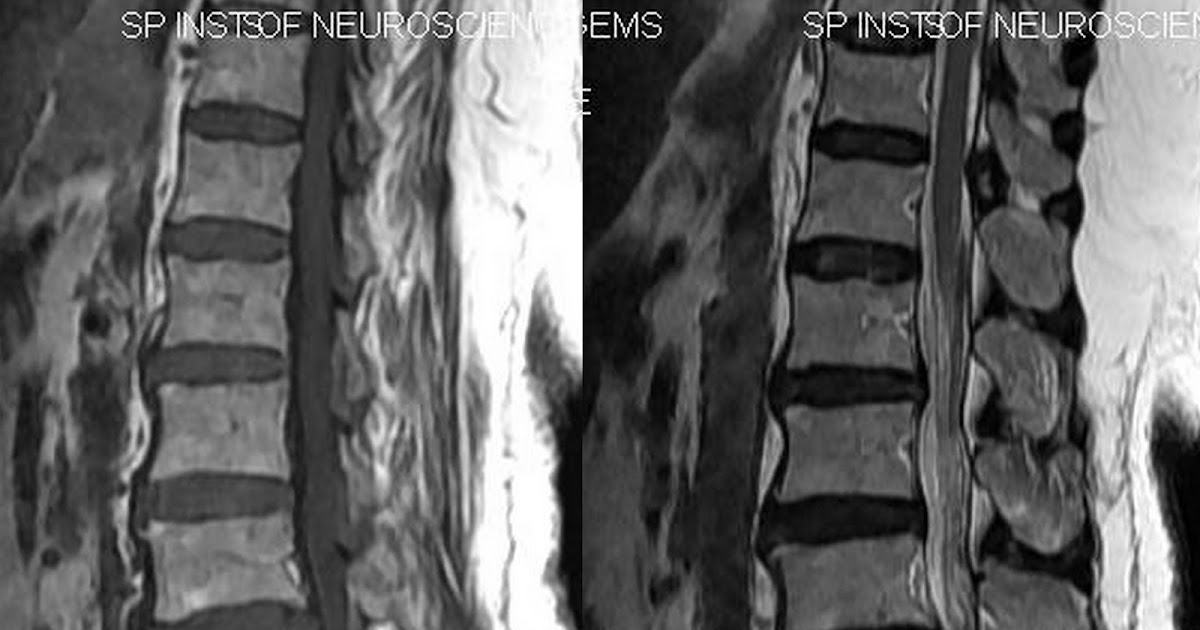

Vacuum Disc Phenomenon Symptoms. Web vacuum disc phenomenon is the accumulation of gas within the intervertebral discs, often a sign of advanced disc degeneration. Web the term “vacuum phenomenon” is used to describe the collection of gas in fissures or clefts that form in the disk as it degenerates. Web a vacuum phenomenon on preoperative imaging studies has been recognized as a radiographic sign of end. Web vacuum disc phenomenon is seen frequently with degenerative disc disease and is characterized by the collection of gas in the. These abnormal spaces produce negative pressure (i.e., a vacuum) where intradisk gas (usually nitrogen) accumulates. While vacuum disc phenomenon may be asymptomatic in some cases, it can also lead to chronic back pain, radiculopathy, spinal instability, and neural compression. Vacuum phenomena have also been observed in herniated disks that are displaced. Web in this paper, we describe the clinical symptoms, diagnosis, and surgical treatment of painful lumbar discs with the vacuum. Web ‘vacuum phenomenon’ or ‘pneumoarthrosis’ term is used when there is air within a joint space.

Web in this paper, we describe the clinical symptoms, diagnosis, and surgical treatment of painful lumbar discs with the vacuum. These abnormal spaces produce negative pressure (i.e., a vacuum) where intradisk gas (usually nitrogen) accumulates. Web vacuum disc phenomenon is the accumulation of gas within the intervertebral discs, often a sign of advanced disc degeneration. Web a vacuum phenomenon on preoperative imaging studies has been recognized as a radiographic sign of end. While vacuum disc phenomenon may be asymptomatic in some cases, it can also lead to chronic back pain, radiculopathy, spinal instability, and neural compression. Web the term “vacuum phenomenon” is used to describe the collection of gas in fissures or clefts that form in the disk as it degenerates. Web ‘vacuum phenomenon’ or ‘pneumoarthrosis’ term is used when there is air within a joint space. Web vacuum disc phenomenon is seen frequently with degenerative disc disease and is characterized by the collection of gas in the. Vacuum phenomena have also been observed in herniated disks that are displaced.